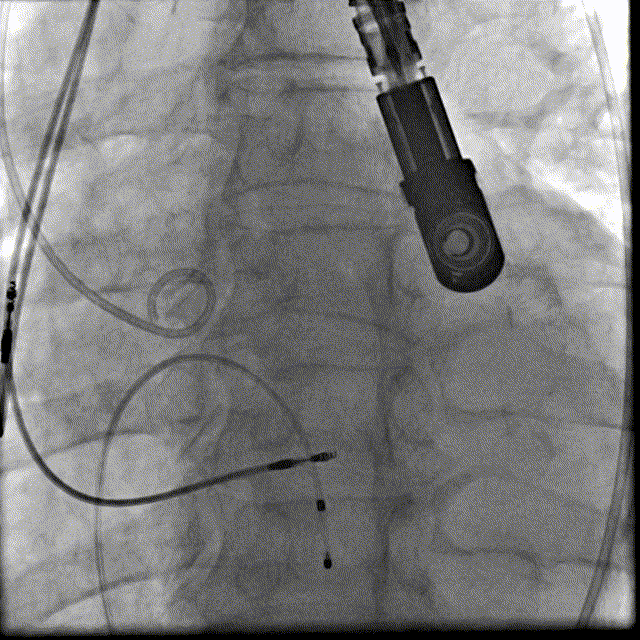

1. 患者取平卧位,常规消毒,铺巾,全麻后,并置入食道超声探头,穿刺左侧股静脉置入6FCordis鞘管,经鞘管将PACEL临时起搏器电极置右心室心尖部

2. 超声引导下穿刺左侧股动脉,置入6F Cook微穿鞘,经鞘管交换为6F pigtail导管置入无冠窦底,随后在超声引导下穿刺右股动脉,置入6F Cordis鞘,给予肝素5000u, 进入Lunderquist导丝,退出6F鞘,置换10F鞘管,置入22FGORE导管鞘套件缓慢推至腹主动脉

3. 在J型导丝指引下,使用6F pigtail造影导管进入左心室,测得主动脉瓣跨瓣压差15mmHg, 升主动脉血压180/40mmHg, 左心室压力165/5mmHg, 交换为特硬导丝Lunderquist至左心室,结合术前冠脉CT和心脏超声测量的瓣环直径大小,选择VitaFlow Liberty™30可回收瓣膜系统送至主动脉瓣环处,在Pigtail导管定位,主动脉根部造影协助指导下,精准定位,以180次/分快速起搏,逐步释放瓣膜,支架释放后退出导管输送系统,猪尾导管行主动脉根部造影示:人工瓣膜深度4mm, 冠状动脉开口未受影响,食道超声提示无主动脉瓣反流。

主动脉根部造影